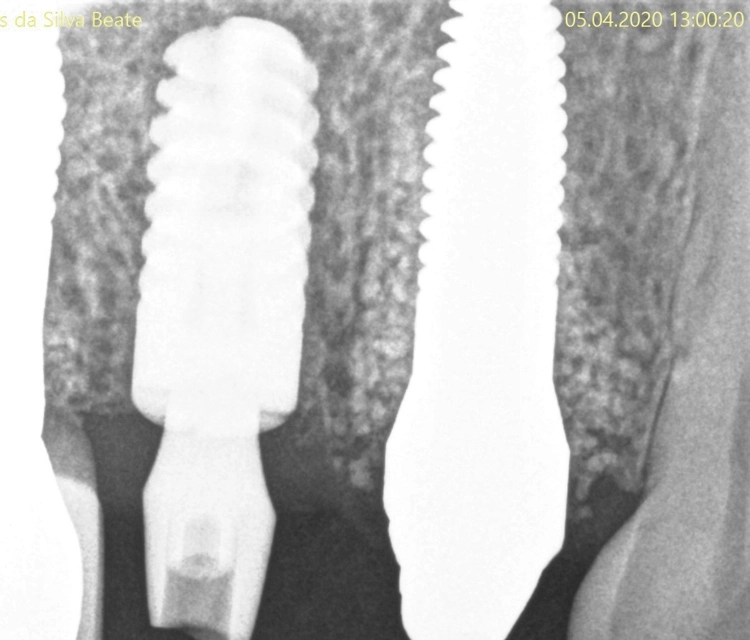

Implantation

Kontrollbild und Röntgenkontrolle ein Jahr und ein Monat nach Socket/Ridge Preservation (Abb. 21 und 22). Der komplette Umbau zu Eigenknochen ist noch nicht abgeschlossen. Die Papillenregeneration zwischen 13/14 und 14/15 ist jedoch deutlich erkennbar.